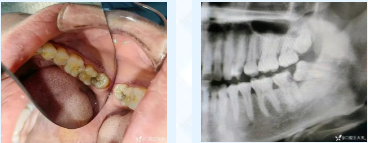

36岁的邹女士深受牙痛困扰,彻夜难眠,遂来到青岛西海岸新区中医医院口腔科就诊。经过详细的口腔检查,发现左下智齿倾斜生长,顶坏了左下第二磨牙,导致牙神经受损,出现冷热刺激痛、夜间痛等。完善曲面断层片等检查,排除手术禁忌后,运用微创拔牙技术顺利实施左下智牙拔除,左下第二磨牙根管治疗+冠修复,为其解决了痛苦。

完善口腔及曲面断层片检查,做出准确的诊断及治疗方案。